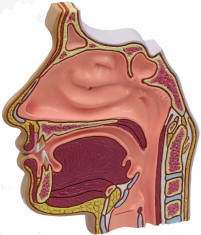

The nose is the means by which we smell or olfaction. This lets us

detect the presence of many things. The Ear, Nose and Throat are

tightly interrelated and are together treated as a medical specialty -

Otolaryngology. Our anatomical models are suitable for medical

schools and are great for patient education. |